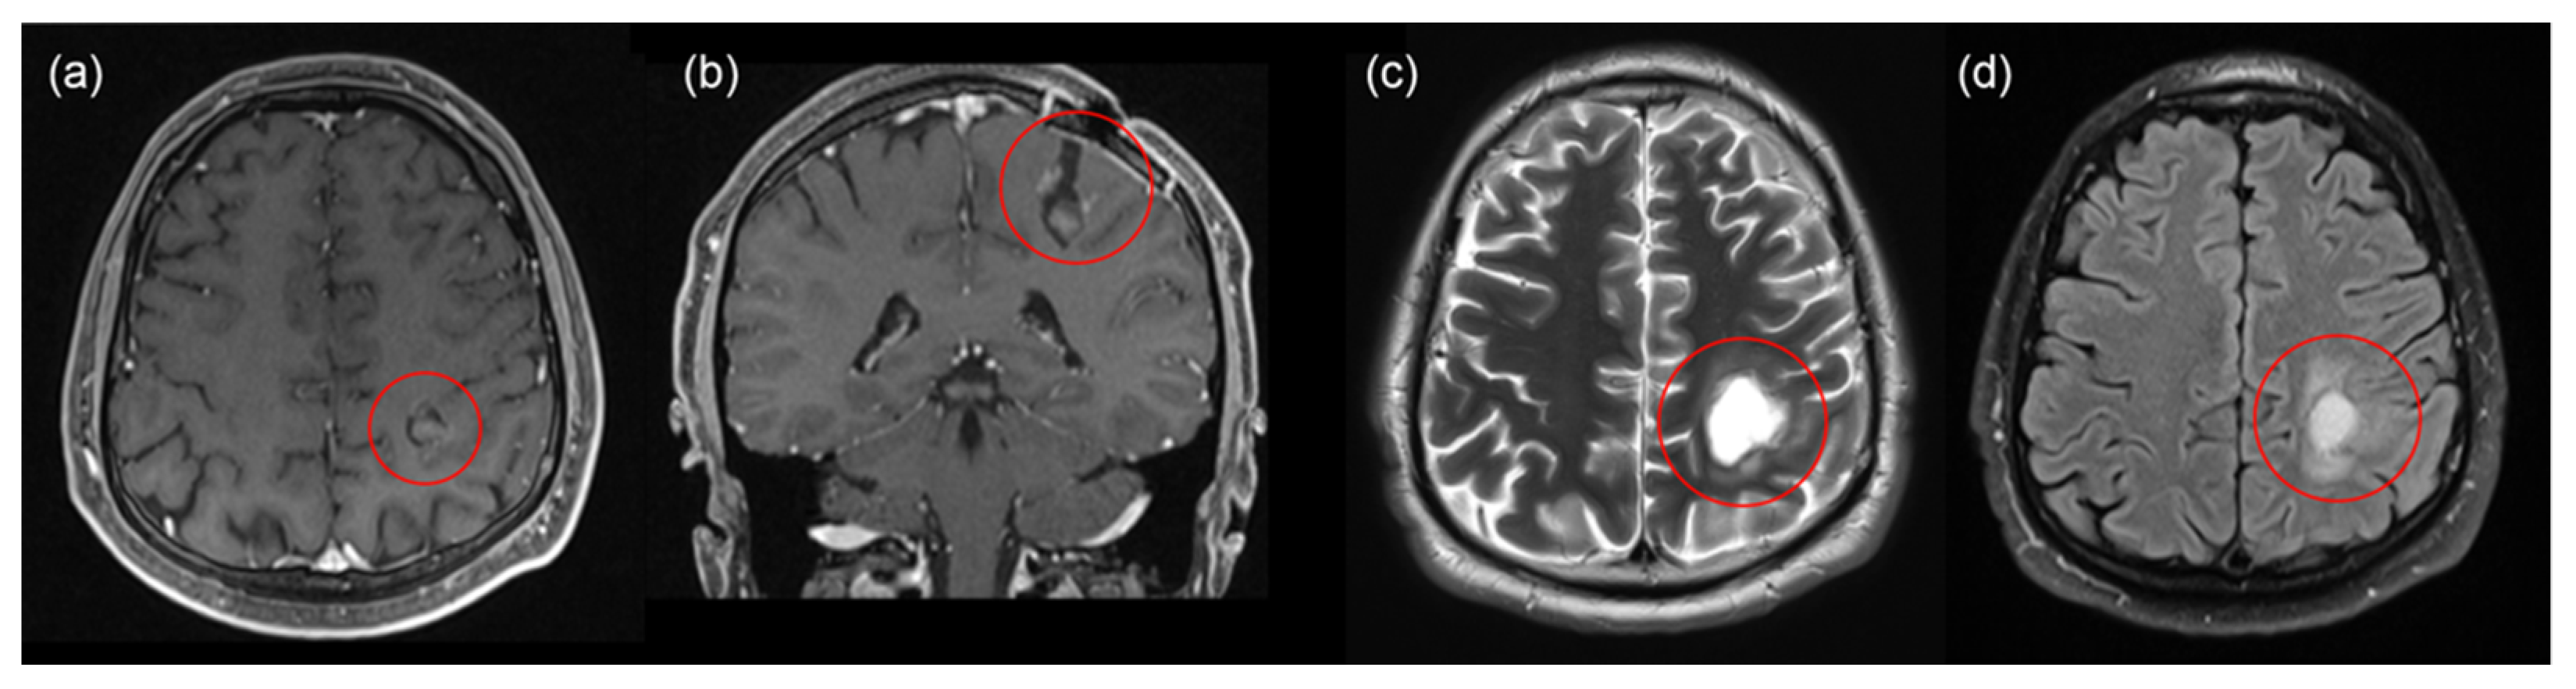

2.1. First Intervention